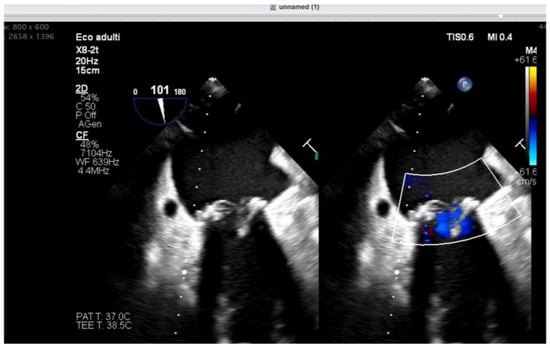

Anesthetic Management of Eosinophilic Granulomatosis with Polyangiitis: A Narrative Review with an Illustrative Case in Cardiac Surgery

by Debora Emanuela Torre and Carmelo Pirri

Background: Eosinophilic granulomatosis with polyangiitis (EGPA), formerly Churg–Strauss syndrome, is a rare necrotizing vasculitis characterized by asthma, eosinophilia, and systemic granulomatosis vasculitis. Perioperative risk is primarily driven by airway hyperreactivity, potential cardiac disease, chronic immunosuppressive therapy, and reported alterations in plasma cholinesterase [...] Read more.

Background: Eosinophilic granulomatosis with polyangiitis (EGPA), formerly Churg–Strauss syndrome, is a rare necrotizing vasculitis characterized by asthma, eosinophilia, and systemic granulomatosis vasculitis. Perioperative risk is primarily driven by airway hyperreactivity, potential cardiac disease, chronic immunosuppressive therapy, and reported alterations in plasma cholinesterase activity. Evidence specifically addressing anesthetic management remains scarce and largely limited to case-based reports. Methods: A focused narrative review was conducted by searching MEDLINE (via PubMed), Scopus, and Embase from inception to January 2026 for publications reporting perioperative anesthetic management in patients with EGPA/Churg–Strauss syndrome. Case reports and case-based descriptions providing explicit anesthetic details were qualitatively synthesized. Results: Available evidence consists predominantly of isolated case reports across heterogeneous surgical settings, including ENT, abdominal, orthopedic, ambulatory, pediatric, and rare cardiac procedures. Recurring perioperative principles include optimization of bronchial disease and continuation of inhaled therapy; minimization of airway stimulation and avoidance of histamine-releasing drugs; selection of induction agents preserving hemodynamic stability in the presence of myocardial involvement; preference for non-depolarizing neuromuscular blockade with quantitative monitoring (and consideration for sugammadex when appropriate); individualized corticosteroid management and multimodal, opioid-sparing analgesia, often supported by regional techniques. Conclusions: In the absence of dedicated perioperative guidelines, anesthetic care for EGPA should be individualized based on clinical phenotype and organ involvement. A structured approach targeting airway protection, cardiovascular stability, safe neuromuscular management, and opioid-sparing analgesia may represent a pragmatic risk-mitigation framework. These considerations are illustrated by an institutional experience in mitral valve surgery. Full article

Show Figures

Figure 1